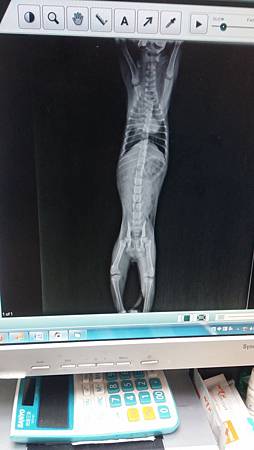

當時於中日動物醫院照X光發現胸腔有氣血胸或肺部破裂,

胸腔有氣血胸或肺部破裂,因X光顯示出肺部及腹部積液,

小貓現仍無法站起,懷疑頸椎處有受傷,

但仍需再評估,懷疑前腳有骨折或脫位(因前肢不正常擺位),